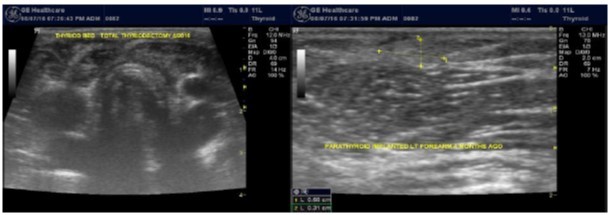

Any nodule with intermediate indeterminate cytology or higher on FNA should go to surgery 23. Among our patients population, one patient with nodular pathology and tertiary hyperparathyroidism was found to have papillary carcinoma of the thyroid during parathyroiectomy. Total thyroidecotmy was done and the patient got forearm implantation of one of the parathyroid glands, Figure 6.

Figure 6.Total thyroidecotmy and forearm implantation of the parathyroid gland

Some experts prefer partial or total thyroidectomy if the cancer is already confirmed before

surgery. However, no consensus exists about partial thyroidectomy 23. Some authors recommend ablation using radioactive iodine (I-131) for high-risk patients with postoperative thyroid replacement therapy but the benefits of administration remain controversial in low-risk patients 23, ,24. Follow up with regular TSH is recommended following complete resection of thyroid cancer. The TSH concentration should be in the target range of 0.5 μU per mL. Greater suppression may be necessary for high-risk patients and those with a metastatic or locally invasive tumor.